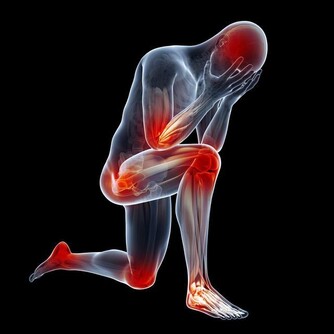

Q1:高尿酸是怎麼來的?

人體尿酸有兩種來源:一是內源性的,是有身體內的氨基酸、核酸等分解而代謝出來,約佔80%;二是外源性的,是有吃的食物中的核苷酸分解代謝而出,佔20%左右。

高尿酸是一種生活方式的疾病,想要降尿酸,不管是吃藥治療,還是飲食上的調整,都要牢記2個原則:減少尿酸生成,促進尿酸排泄。

減少尿酸的生成,在生活中主要體現在飲食的調整上,不單單要限制高嘌呤食物的攝入,比如少吃或者不吃海鮮、動物的內臟,少和白酒啤酒等,還要少吃高糖、高脂肪的食物。因為血樣、血脂和血尿酸之間具有相互促進的作用。

第二、促進尿酸的排泄

促進尿酸排泄的辦法,除了大家都熟悉的多喝水之外(每天喝水量不少於2000毫升),還可以多吃點鹼性食物,比如適當喝點蘇打水。

除此之外,要多運動,控制自己的體重。因為減肥和運動也是有利於降尿酸的行為。但是需要提醒大家的是,減肥需要循序漸進,切莫心急。而運動也要選擇適合自己的運動項目,根據自己的身體情況來選擇,避免運動強度過大,造成不必要的身體傷害。